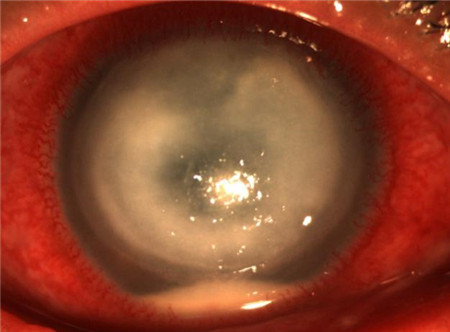

當角膜產生疤痕之后,會因此變得渾濁,將對視力產生嚴重影響,比如視物模糊、散光等。此外,若不及時控制炎癥還有可能引起眼內發炎,甚至波及整個眼球。所以角膜潰瘍這個眼疾應該及早治療,“拖延”是解決不了問題的。

雖然角膜潰瘍的成因以及類型都比較多,但他們的癥狀大體是差不多的,眼痛、畏光、流眼淚、眼睛發紅、分泌物增多等都是其典型的癥狀。當病變發生在角膜的中央,還可能出現視物模糊、視力下降。當眼睛出現這些不適癥狀時,不要自行購買眼藥水治療,更不要拖著不管,而應馬上前往醫療進行診治。

對于角膜潰瘍,若能及時治療可防止疤痕形成而避免視力受到影響。北京希瑪林順潮眼科醫院認為,角膜潰瘍治療的關鍵在于要找到致病原因,通過及時消炎來促進上皮的愈合。針對非感染性的角膜潰瘍,需要采用抗生素和類固醇藥物來預防感染以及消除炎癥。